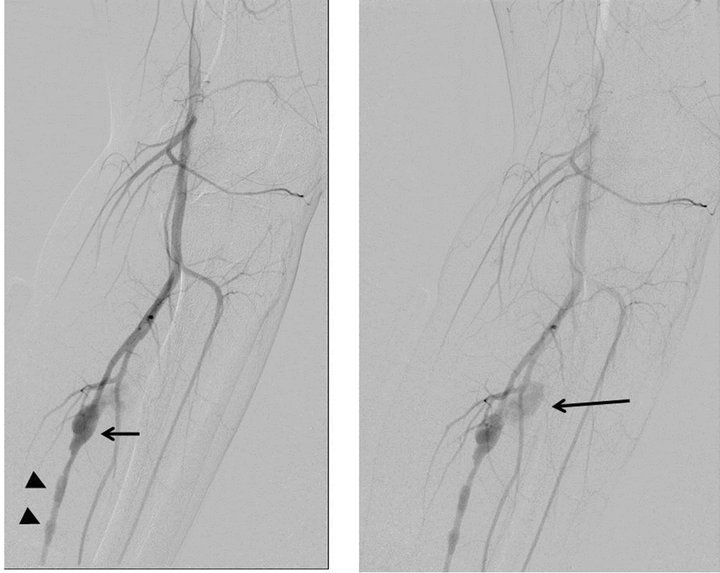

Left superficial femoral arteriogram showed a fusiform aneurysm of the posterior tibial artery with a segmental wall irregularity distal to the aneurysm (Figure 3(a)). Late arterial phase of the arteriogram also revealed an extravasation from the aneurysm (Figure 3(b)). Because we could easily pass the catheter through the aneurysm and irregular segment using microcatheter system (Renegade-18, Boston Scientific Japan, Tokyo, Japan/0.016-inch Radifocus GT wire, Terumo, Tokyo, Japan), we planned an internal trapping of the abnormal segment by the distal-to-proximal fashion. We initially deployed three detachable coils (Orbit Galaxy 5.0 mm - 15 cm, 4.0 mm - 12 cm, 4.0 mm - 12 cm, Johnson and Johnson, Tokyo, Japan) at the distal end of the irregular segment. Then we added a detachable coil (Matrix2 8.0 mm - 30 cm, Boston Scientific Japan, Tokyo, Japan) within the aneurysm followed by three coils (Matrix2 5.0 mm - 15 cm, Orbit Galaxy 3.5 mm - 7.5 cm, 3.5 mm - 7.5 cm) deployed at just proximal to the aneurysm (Figure 4).

After the embolization, the lesion was completely divided from the arterial supply of the left lower leg (Figure 5). Distal left posterior tibial artery of normal appearance was well-supplied via muscular branches. In

Figure 3. (a) Arterial phase of the left superficial femoral arteriogram (digital subtraction angiography) shows an irregular fusiform aneurysm (arrow) of the posterior tibial artery. Segmental wall irregularity is also shown distal to the aneurysm (arrowheads); (b) An extravasation (arrow) from the aneurysm was shown on the late arterial phase.

Figure 5. (a), (b) Left superficial femoral arteriograms show a complete disappearance of the abnormal segment including fusiform aneurysm. Distal posterior tibial artery is well-visualized by collaterals.